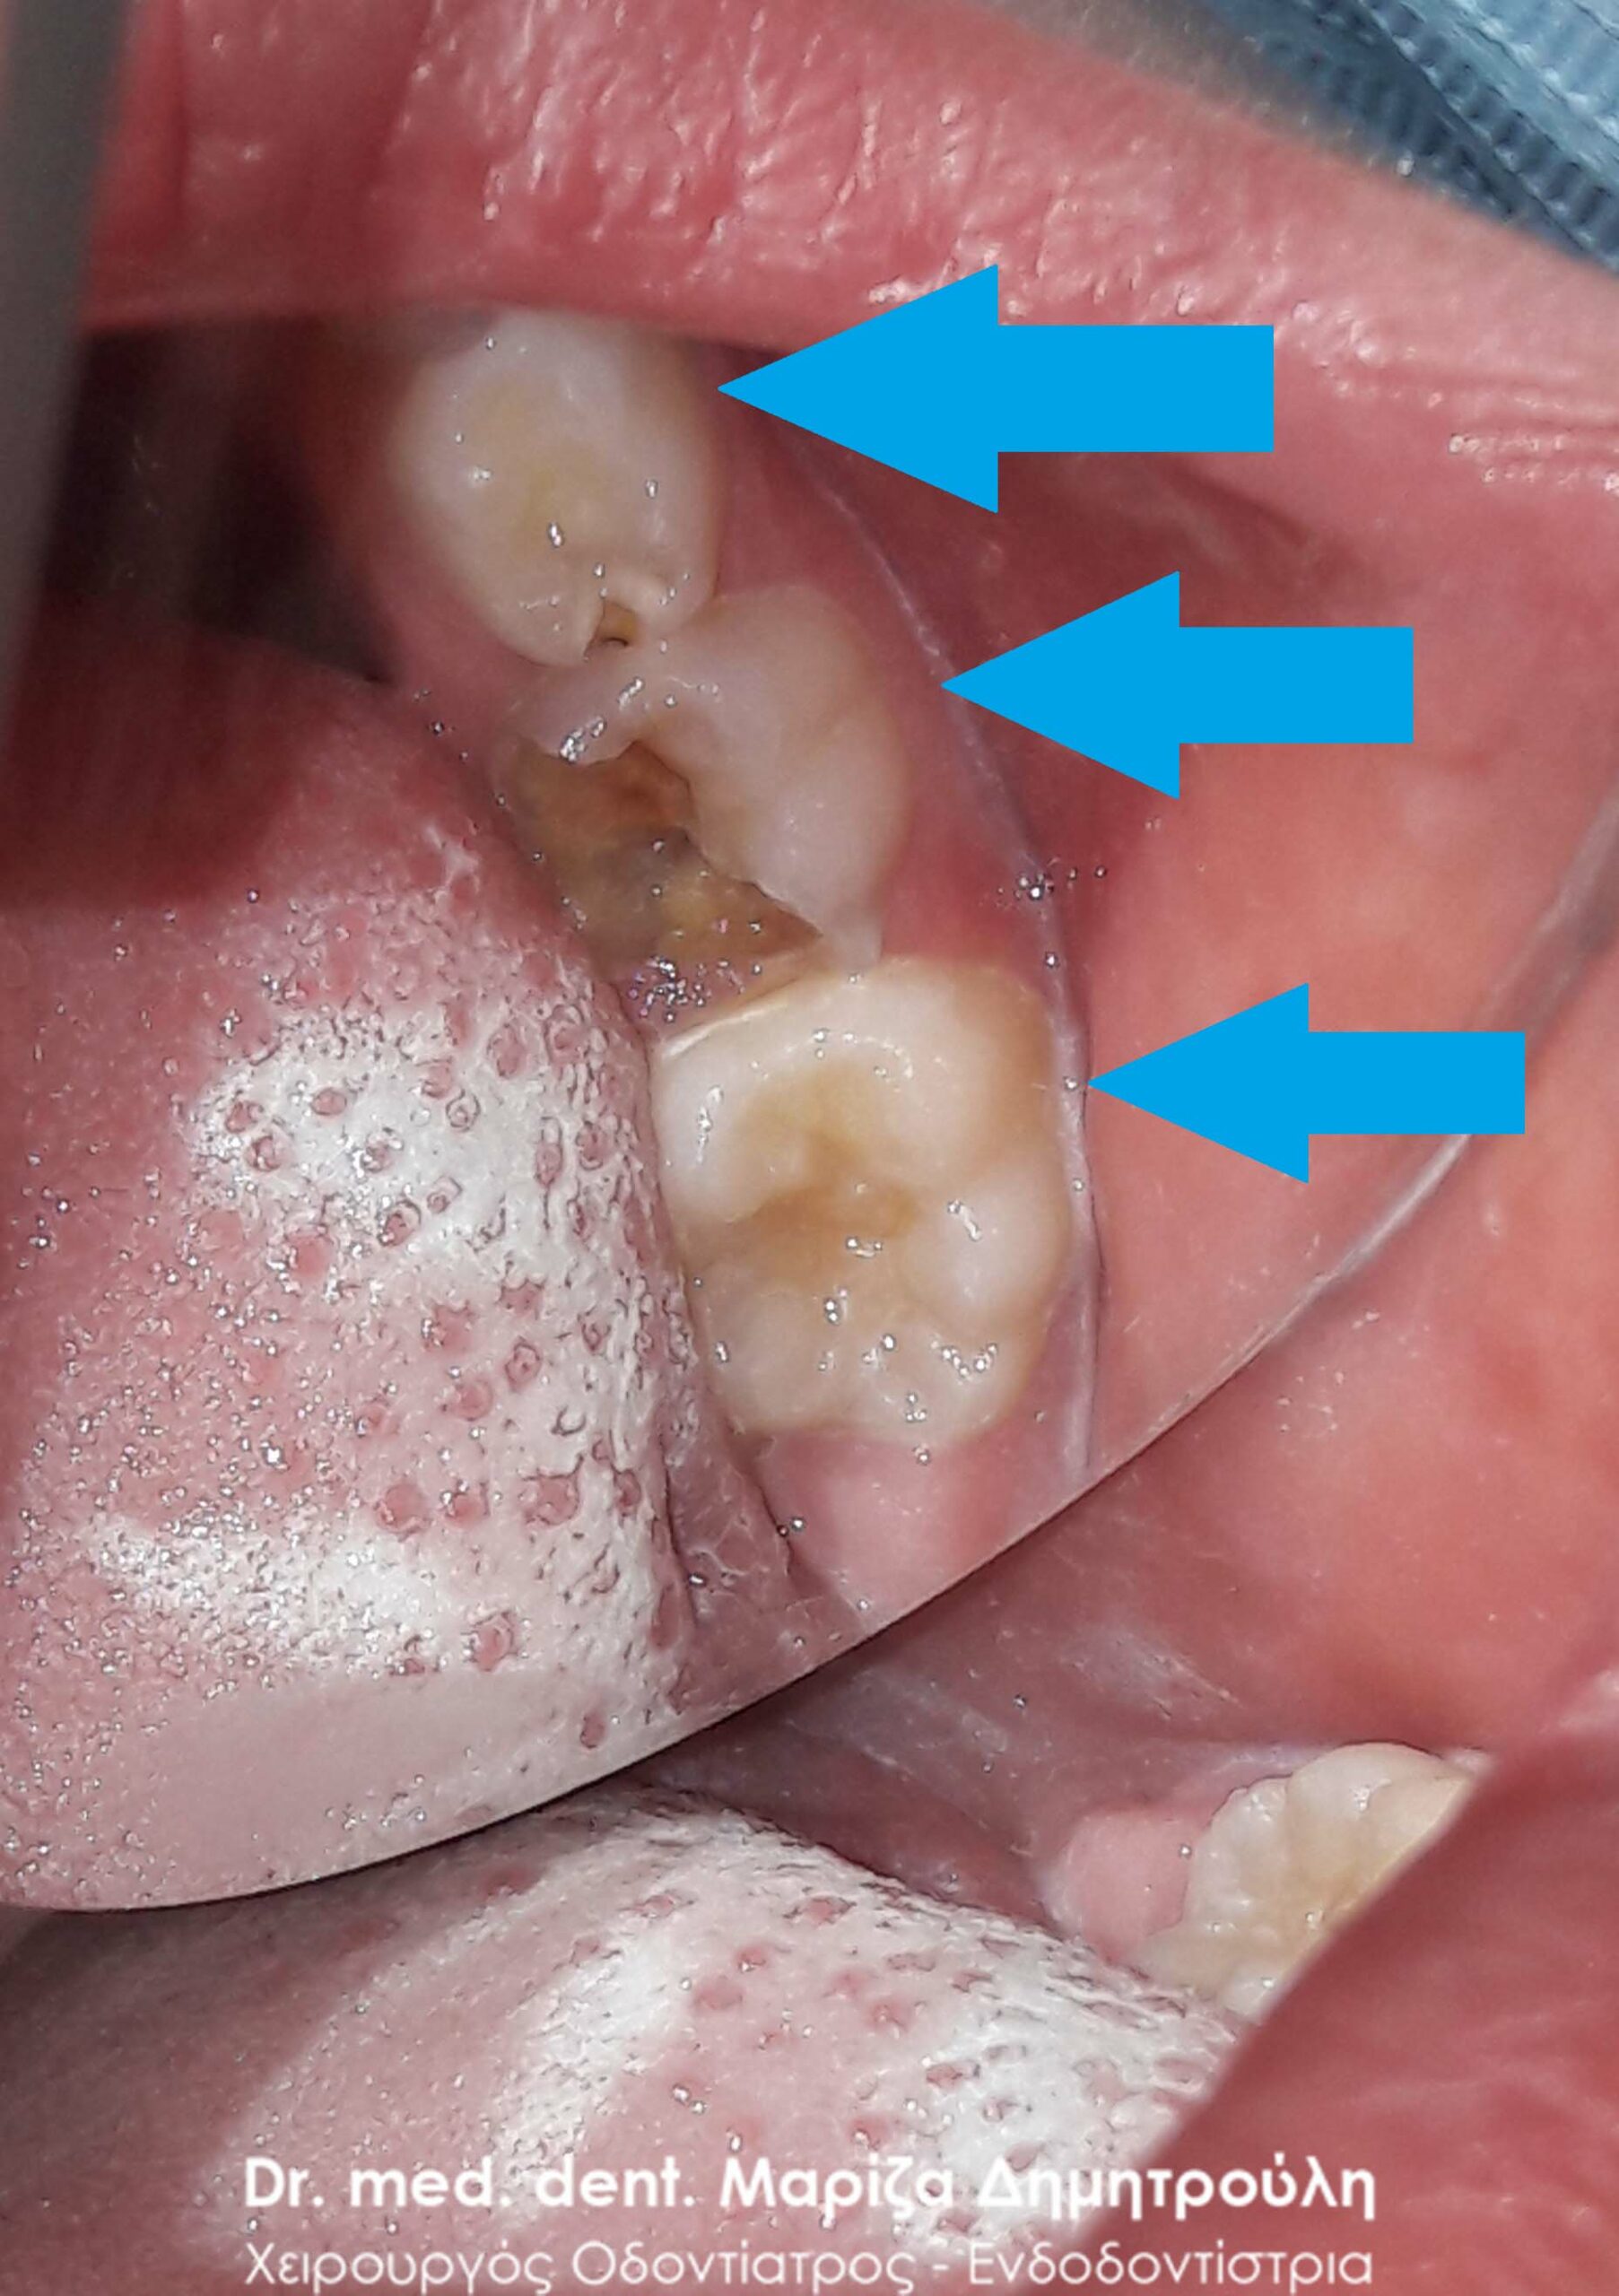

Dental filling of primary tooth

BEFORE